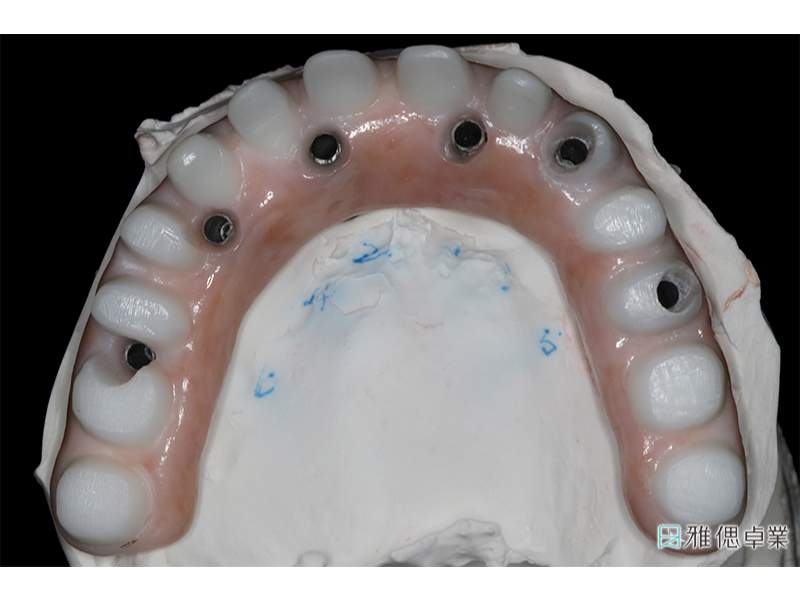

精密設計基座上的正式假牙

基座上每顆正式假牙皆是單獨的,方便清潔與維修

假牙模型上顎